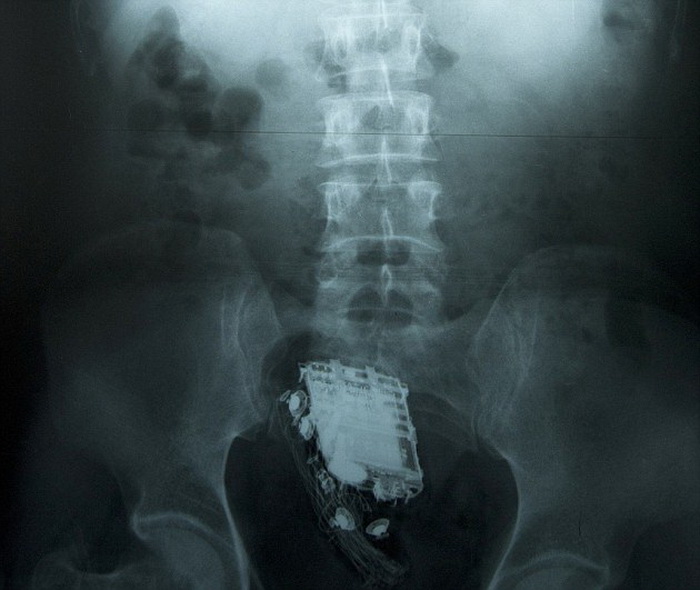

Педесетгодишниот затвореник, кој отслужува десет годишна казна, се наоѓал во затворот Великада во градот Котте, во кој е забрането внесување мобилни телефони. По инцидентот, затвореникот бил пренесен во болница каде му биле направени рендгенски снимки, по што мобилниот телефон му бил отстранет. По два дена бил отпуштен од болница.